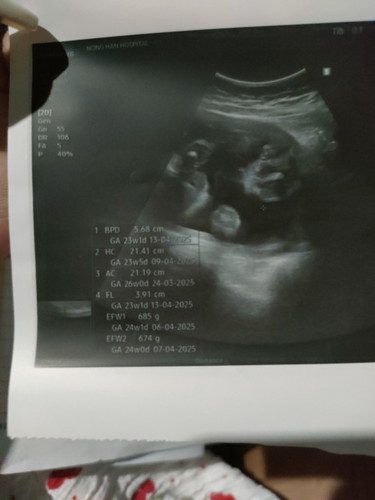

ใบซาวคือรูปอะไรคะ แล้วอันไหนนํ้าหนักน้องคะ24+2

ถ้าอายุครรภ์24+2 ดูตรง EFW2 674g. คะ